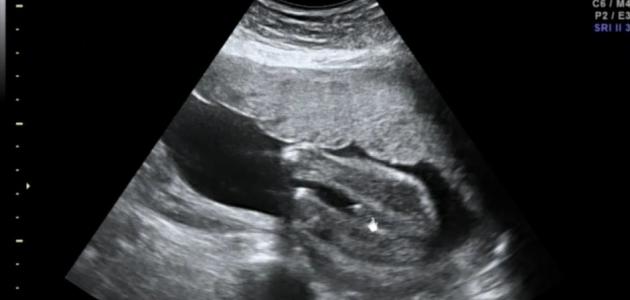

- السونار (الموجات فوق الصوتية):

- يُمكن الكشف عن جنس الجنين باستخدام السونار بعد الأسبوع 18-20 من الحمل.